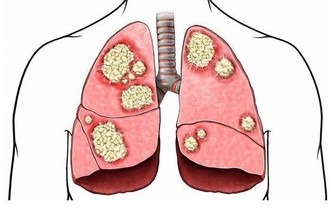

前列腺癌是男人中發病率最高的惡性腫瘤,他的發病年齡高峰期在65歲,

但是隨著男性生活習慣的改變,飲食的西化,前列腺癌的發病率逐漸年輕化。

男人在50歲以下患前列腺癌從1998年到2008年,10年增加了60%,50歲以上的男性,每增加五歲,發病風險增加一倍。50歲以上的男性,是前列腺癌的高危人群。前列腺是一種和年齡密切相關的惡性疾病,年齡越高的男性,發病風險越高。